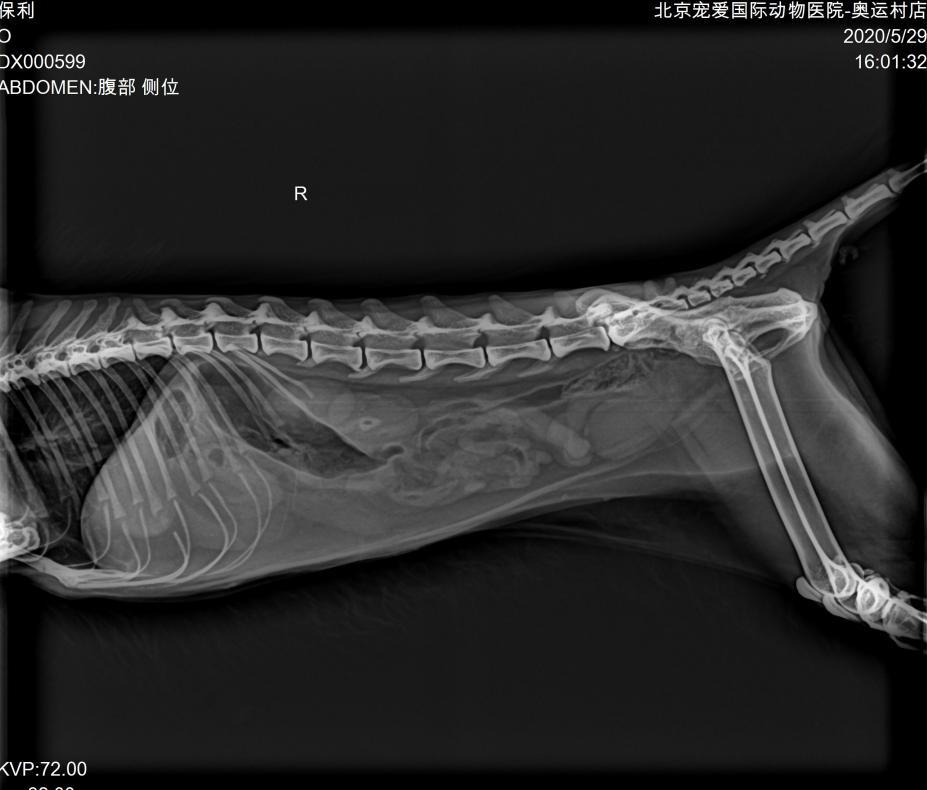

DR:

DR显示胃肠道空虚,未见阳性异物。

腹部彩超:

超声显示双肾萎缩,皮髓质分界减弱,提示慢性肾病;肝脏整体回声增强,提示肝脏脂质沉积;胆泥淤积,胆管堵塞。